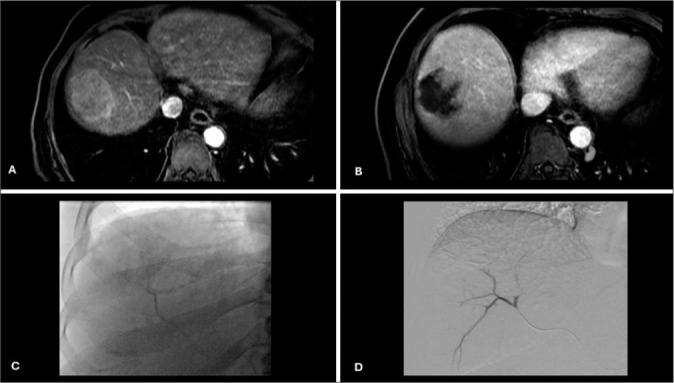

Objective: The objective of this study was to evaluate complete contrast staining (CCS) of HCC during drug-eluting bead transarterial chemoembolization (DEBTACE) first session for response prediction.

Methods: Forty-one patients with solitary HCC who underwent DEBTACE were retrospectively enrolled and divided into two groups based on contrast staining of HCC using two-dimensional (2D) fluoroscopy during the first session of DEBTACE. Both groups underwent one or two sessions of DEBTACE to achieve a complete response. Responses were evaluated using the modified Response Evaluation Criteria in Solid Tumors. A comparison of the complete response between the CCS and non-CCS groups was performed, and the prediction value was studied.

Results: CCS in 2D fluoroscopy during the first session of drug-eluting bead chemoembolization was observed in 22 (53.7%) patients. Well-defined HCC and super-selective chemoembolization were significantly associated with CCS. Complete response was observed in 54.54%, 90%, and 95.45% of CCS patient groups after the first session, second session, and cumulative sessions of TACE, respectively. Complete responses were 10.52%, 29.41%, and 36.84% in the non-CCS group after the first, second, and cumulative sessions of TACE, respectively.

Conclusion: CCS of HCC using 2D fluoroscopy during DEBTACE is a predictor of a favorable response after two sessions of treatment.